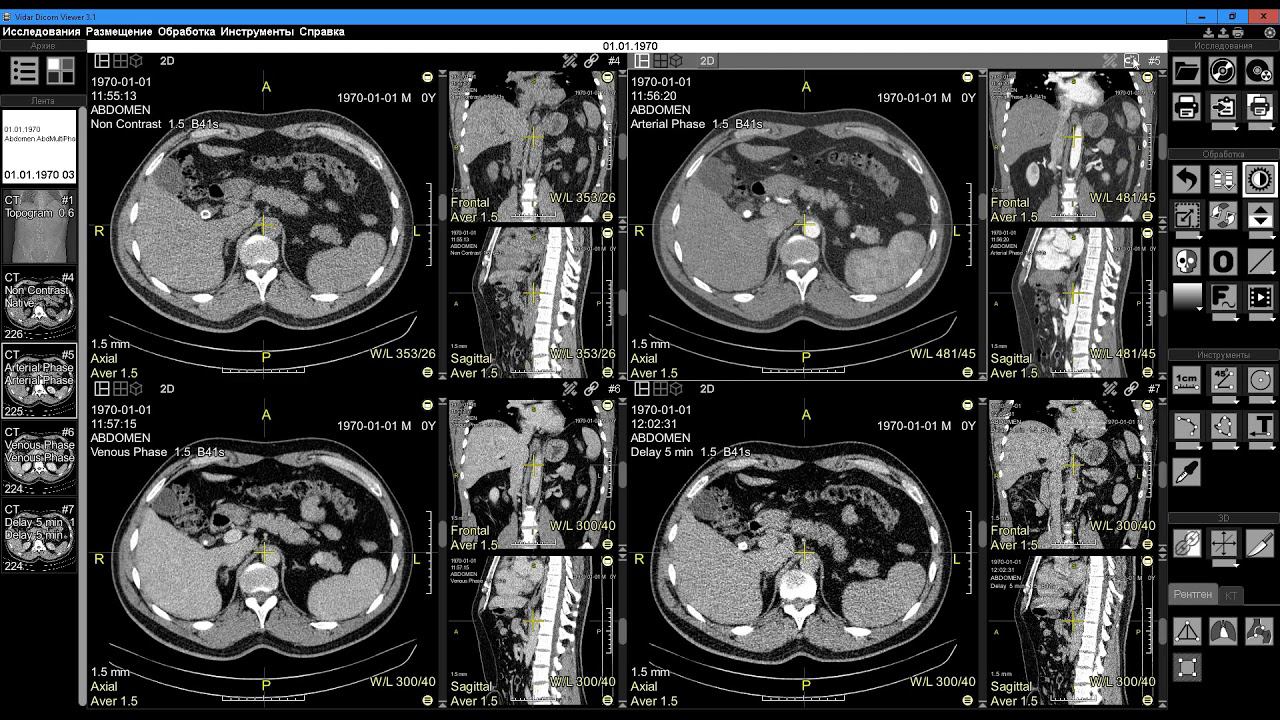

Как открывать кт файлы

Как открывать кт файлы 115 фото